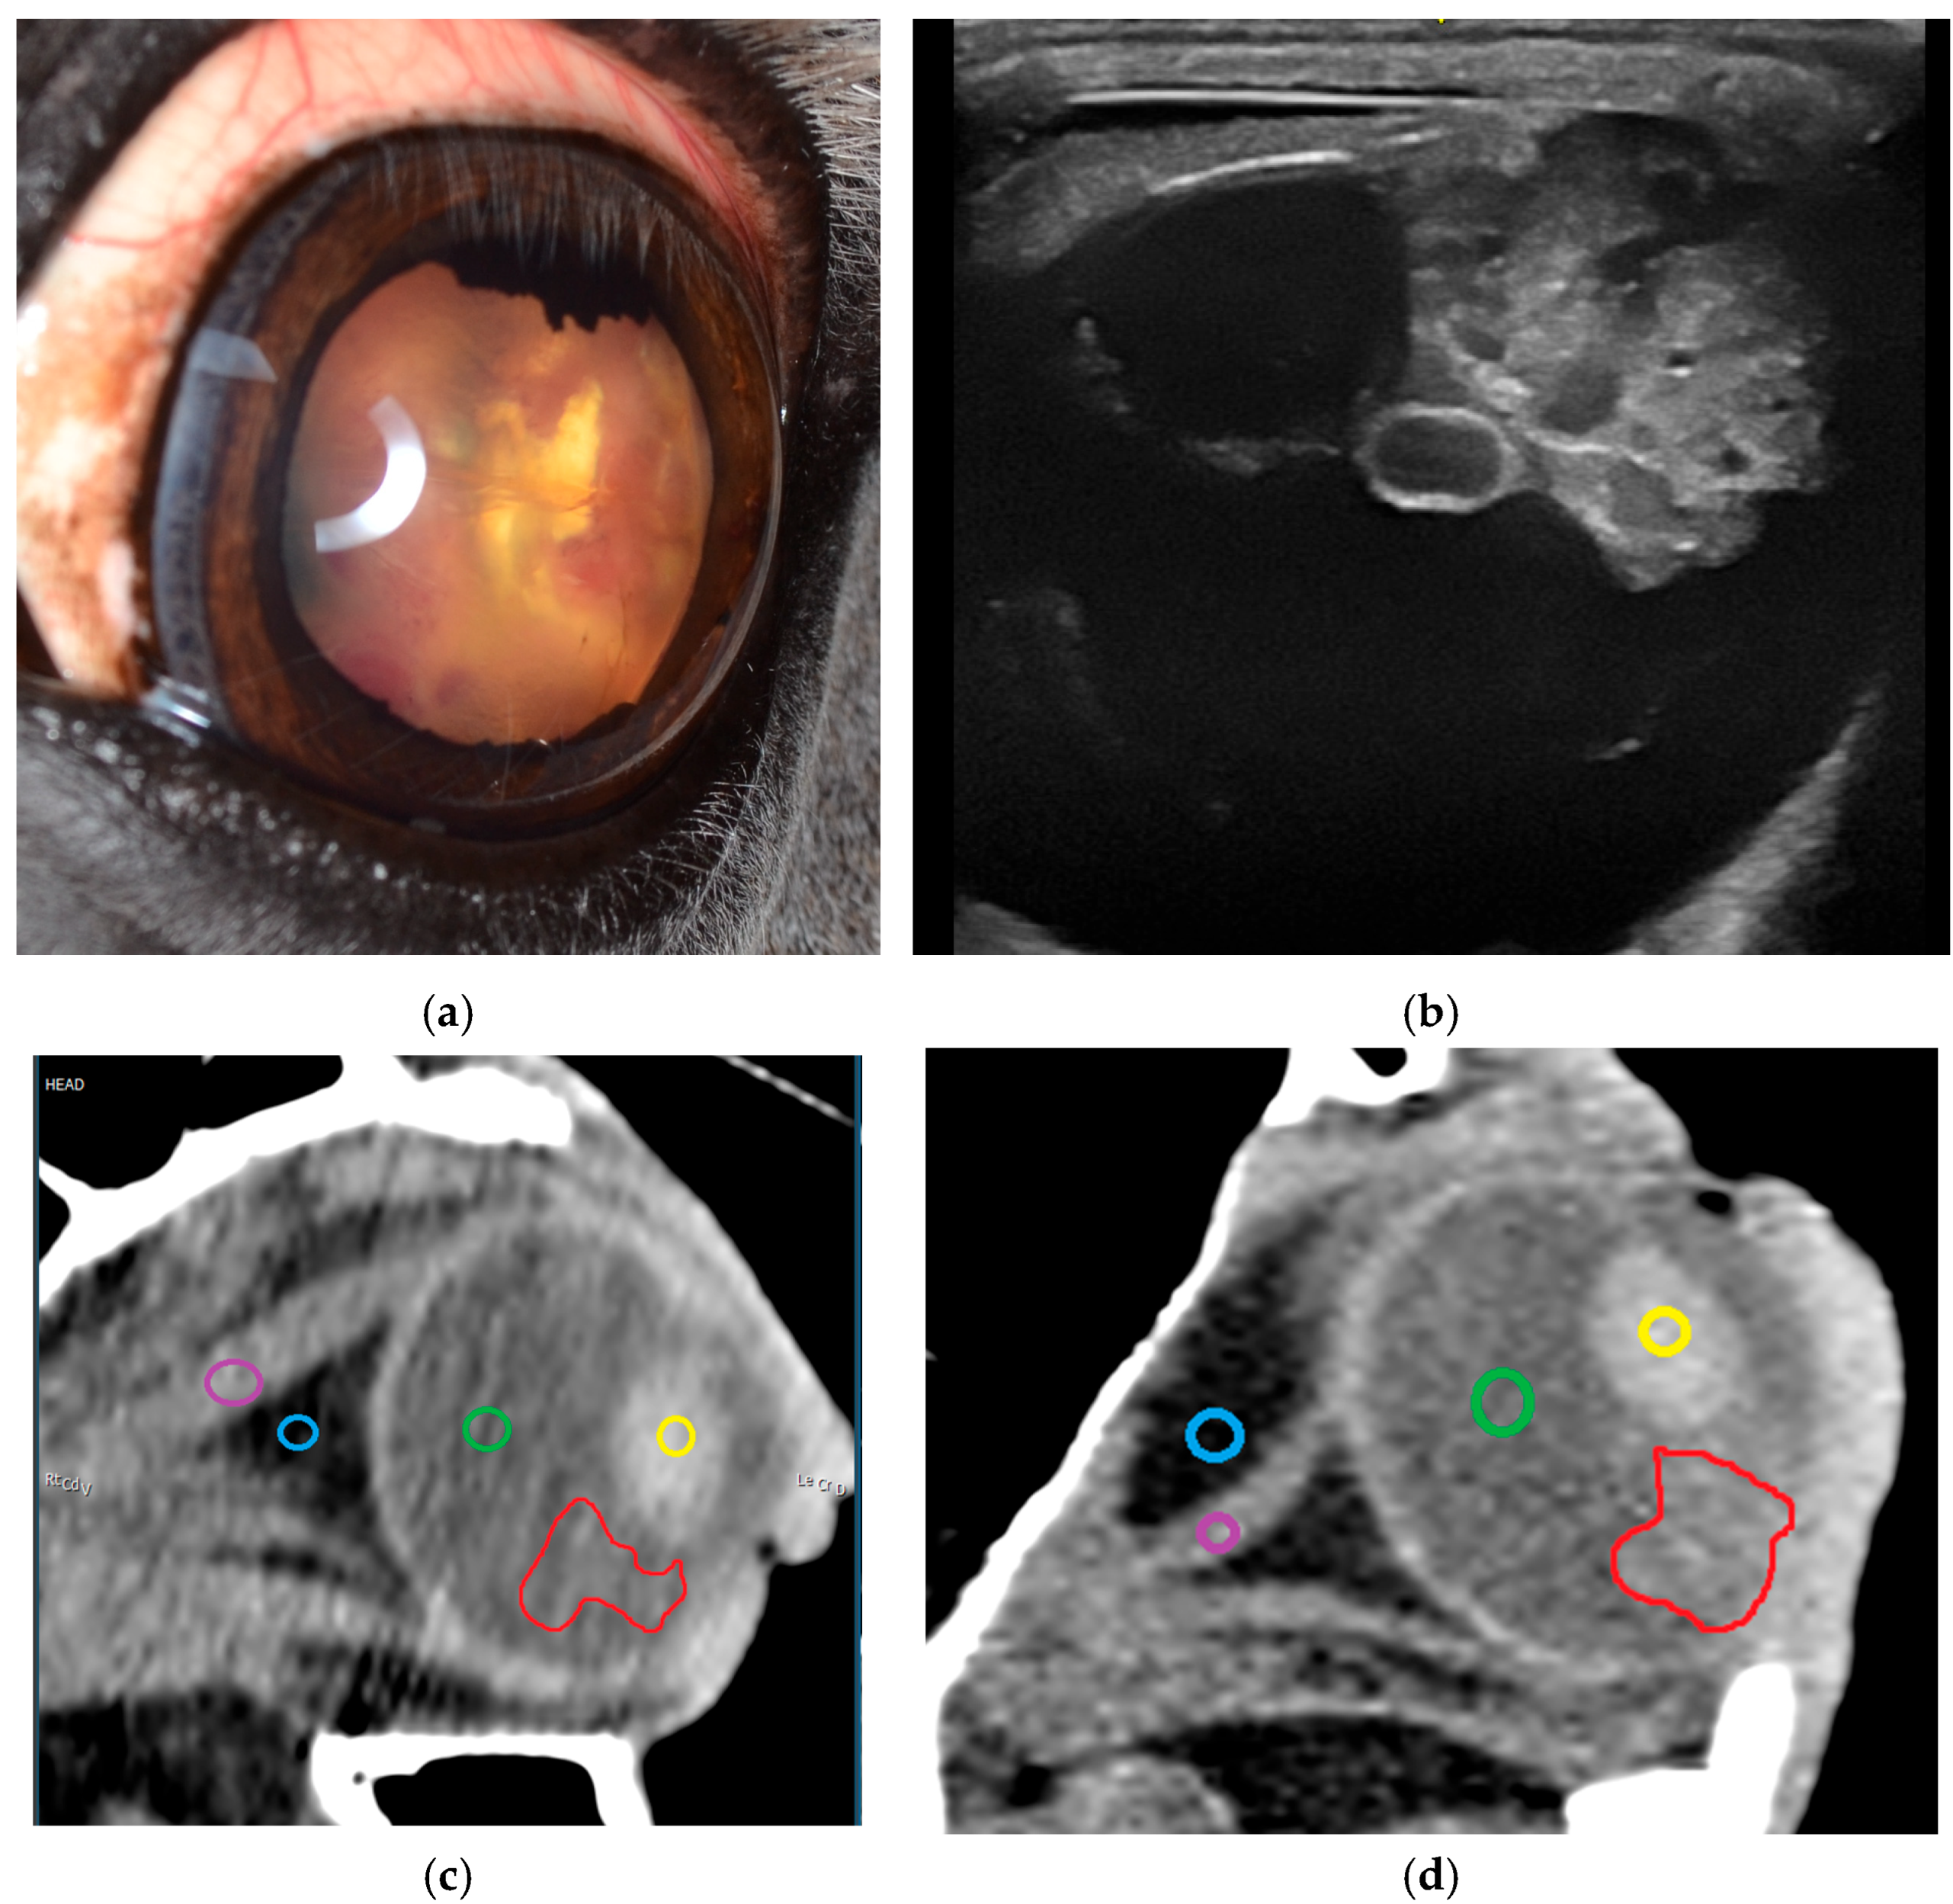

3.2.1. Ultrasonography

3.2.2. Sectional Imaging

4.2. Uveal Intraocular Tumors: Melanocytic Neoplasia